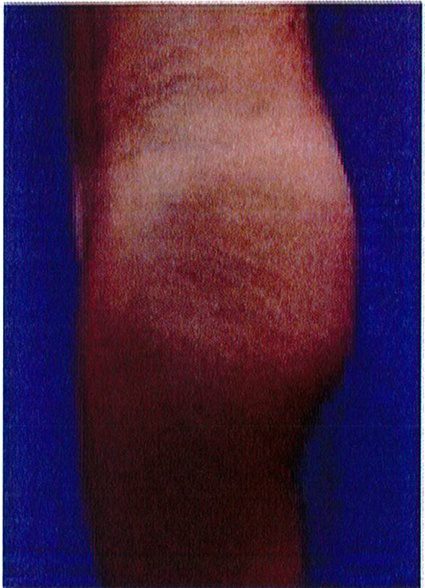

Hình. 18.. (A) Hình anh trước và (B) và sau phẫu thuật làm đầy mông của bệnh nhân được đặt khối implant dưới cân thể tích 225 mL, hai bên.

Bệnh nhân 31 tuổi tiền sử khỏe mạnh, có chỉ định nâng mông bằng implant do thiếu hụt thể tích. Hai khối anatomic implant 225 mL polyurethane dạng gel được đặt ở vị trí dưới cân. Sau phẫu thuật không ghi nhận biến chứng trong suốt quá trình hồi phục, vết mổ liền tốt (Hình 18).

Hình. 19. . (A) Hình anh trước và (B) và sau phẫu thuật làm đầy mông của bệnh nhân chùng da vùng mông tương đối nhiều. Bệnh nhân được đặt khối implant dưới cân thể tích 330 mL ở hai bên.